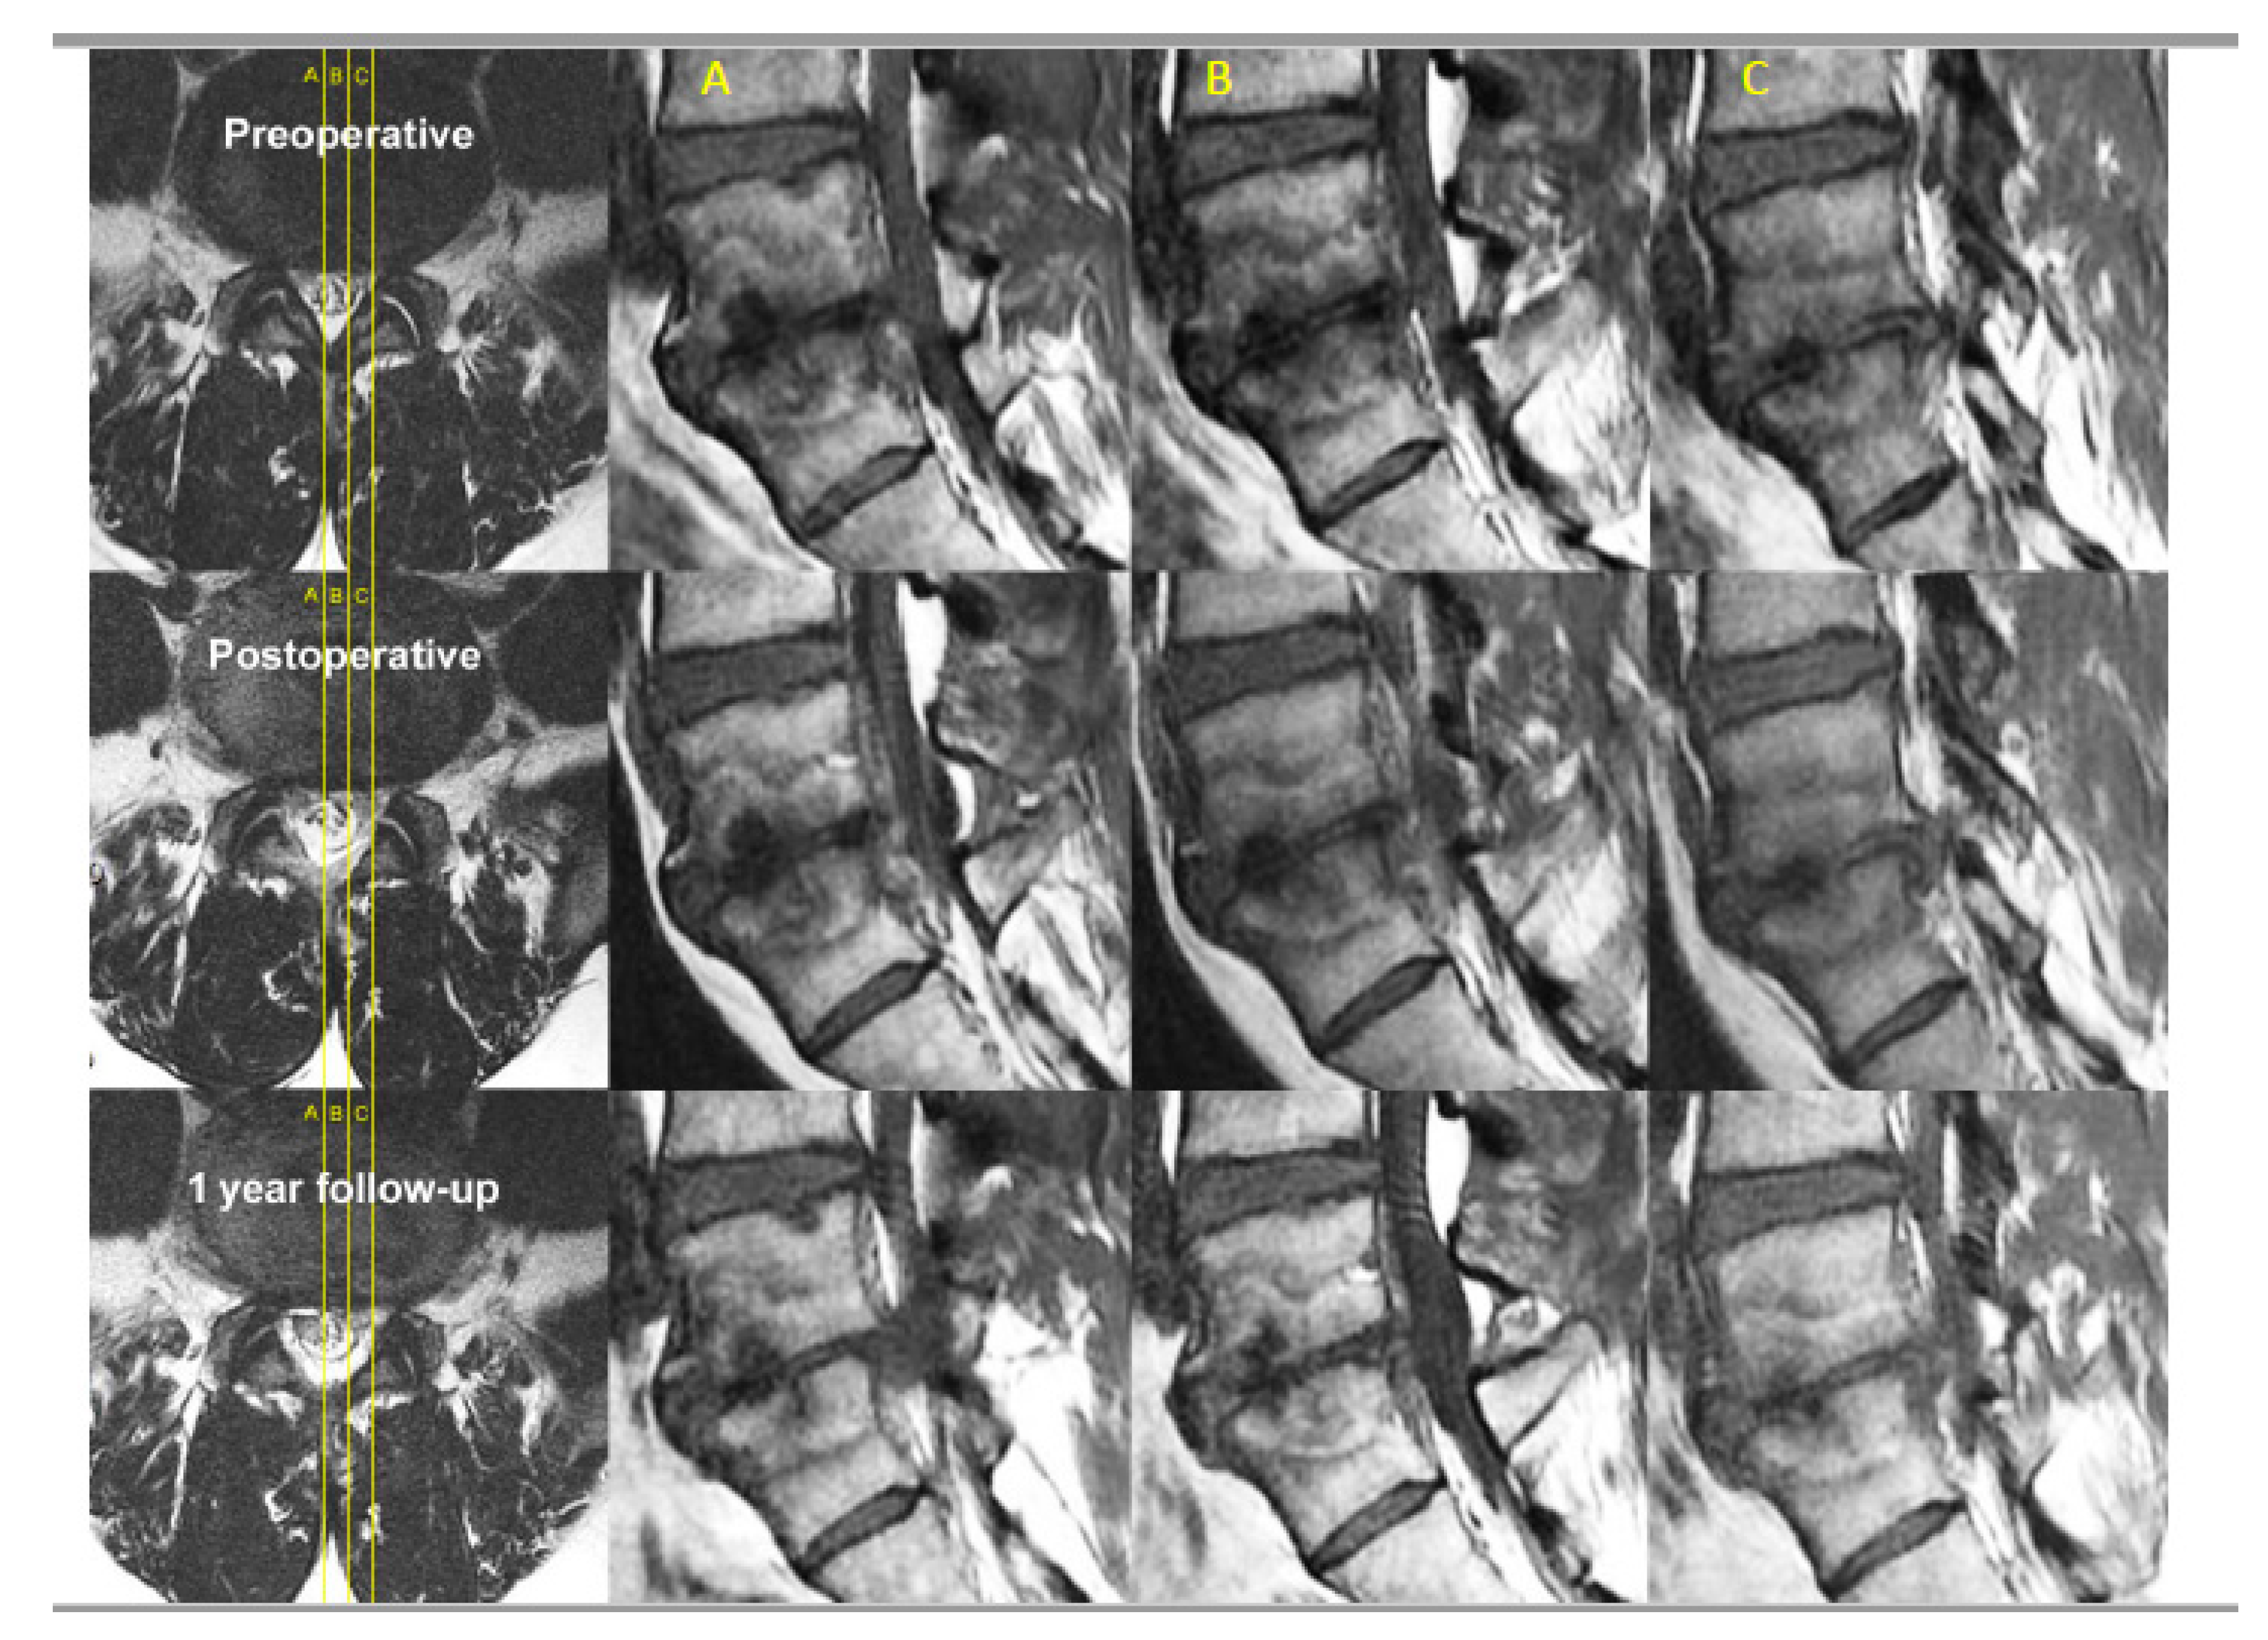

- Kim, H.S.; Adsul, N.; Yudoyono, F.; Paudel, B.; Kim, K.J.; Choi, S.H.; Kim, J.H.; Chung, S.K.; Choi, J.-H.; Jang, J.-S.; et al. Transforaminal Epiduroscopic Basivertebral Nerve Laser Ablation for Chronic Low Back Pain Associated with Modic Changes: A Preliminary Open-Label Study. Pain Res. Manag 2018, 2018, 6857983. [Google Scholar] [CrossRef] [PubMed]

4.2. Ablation of Neuropathic Basivertebral Nerve and Sinuvertebral Nerve